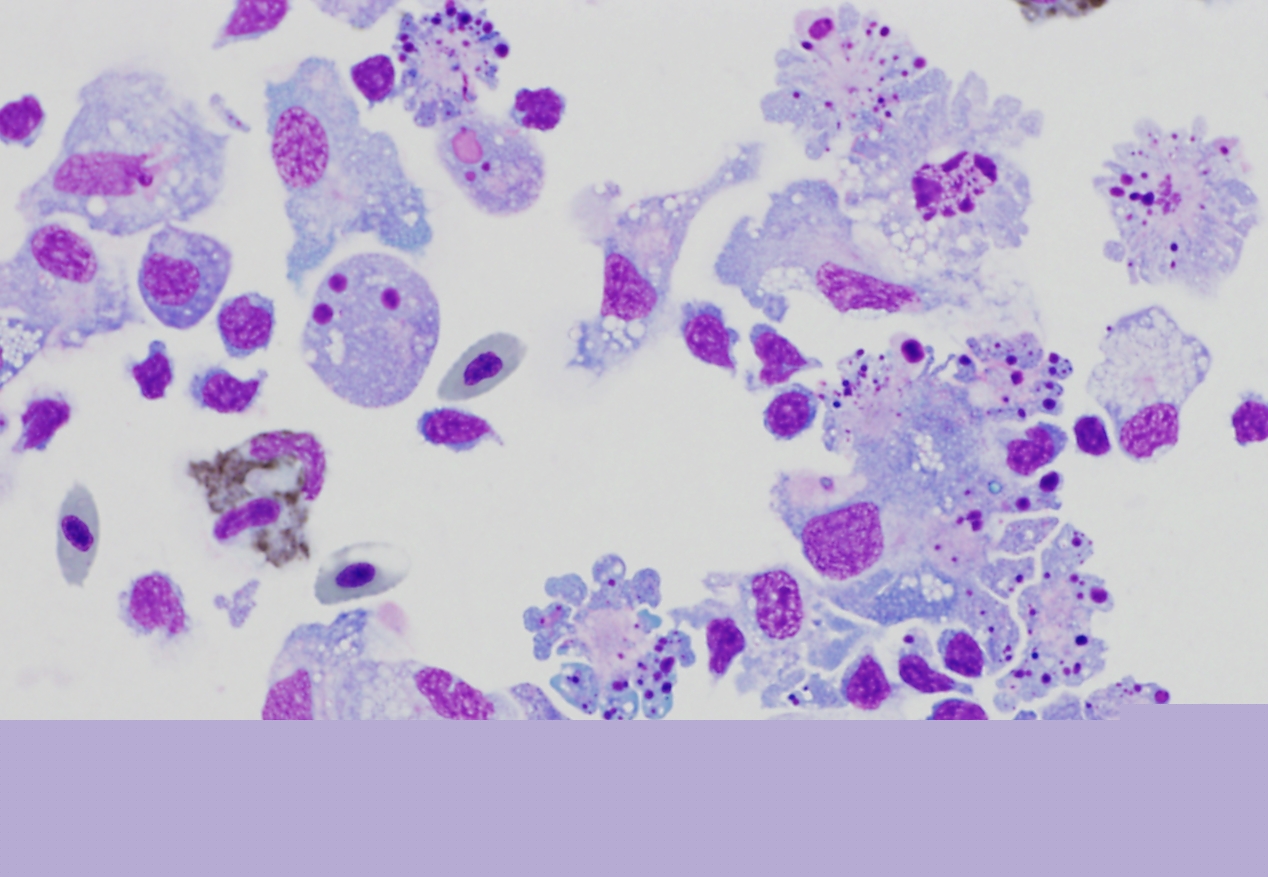

Fotografias ao microscópio de células a morrer, por apoptose, em consequência de exposição à toxina AIP56

(Imagem com maior resolução disponível se solicitada)